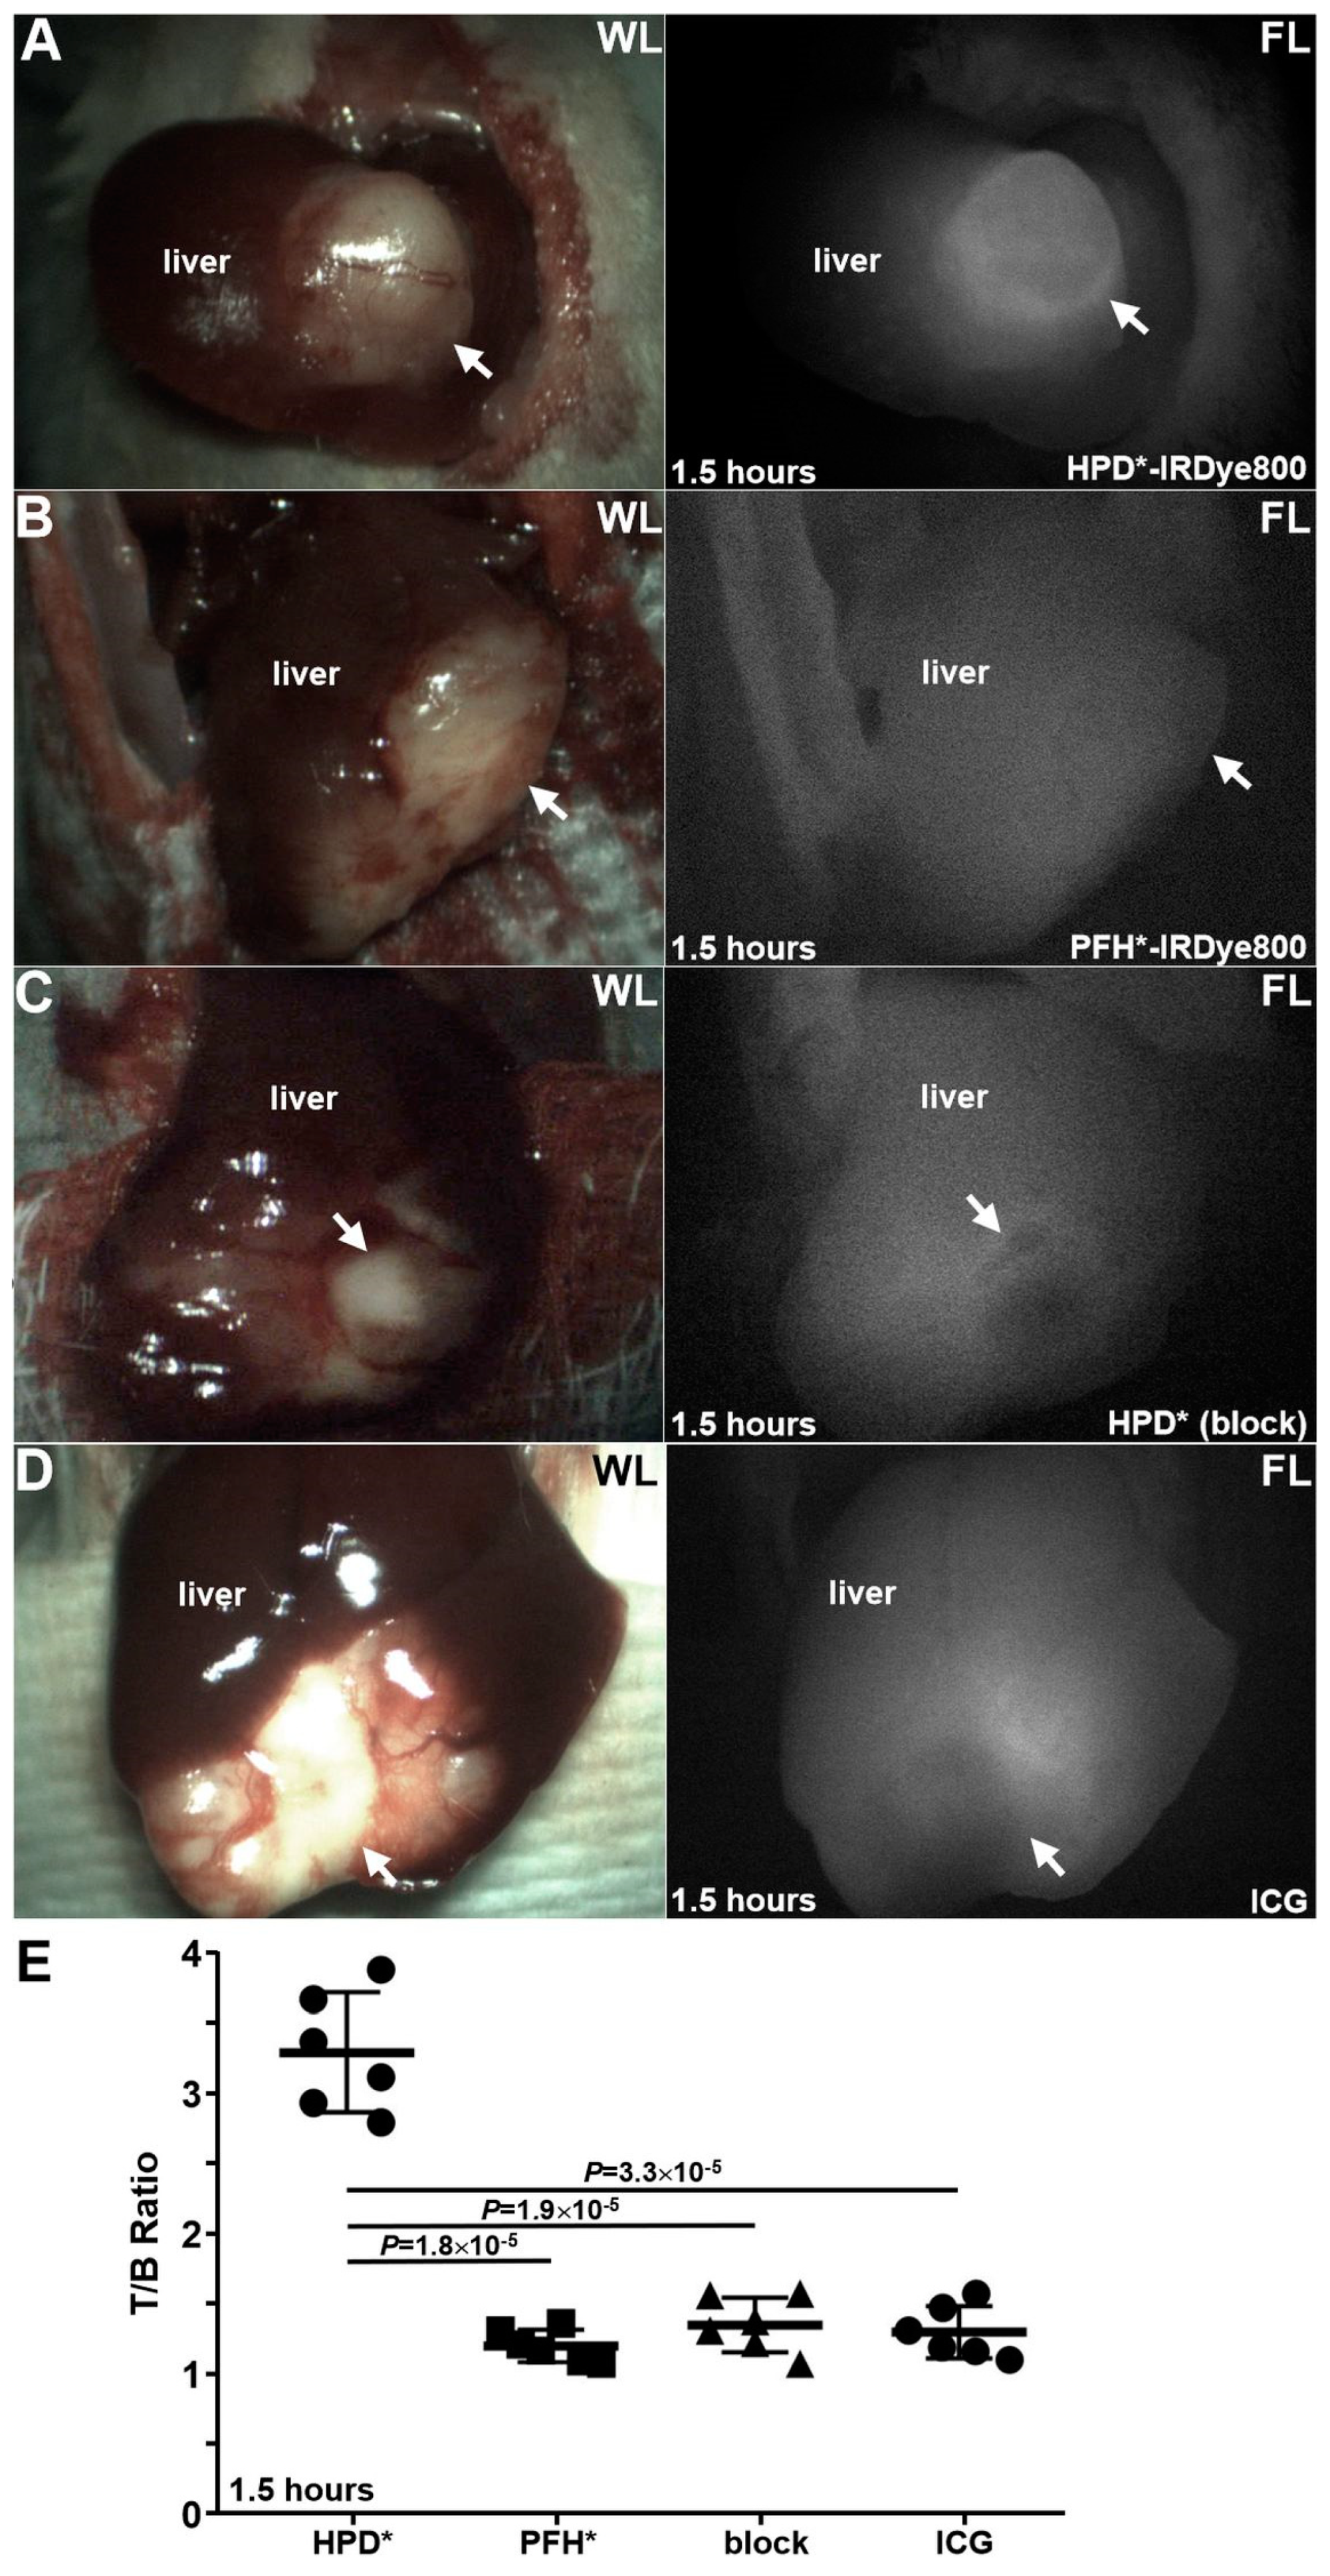

3.5.1. Detection of Primary Tumor